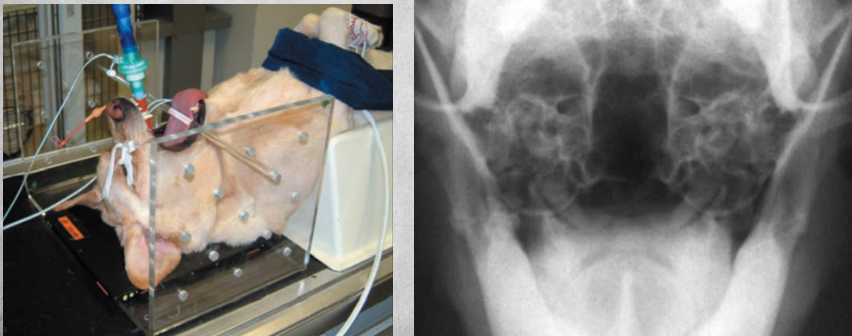

Rostrocaudal closed mouth for viewing…?

the frontal sinus

position such as in picture

Rostrocaudal open mouth for viewing…?

Tympanic bullae

30 degree angle between beam and hard palate